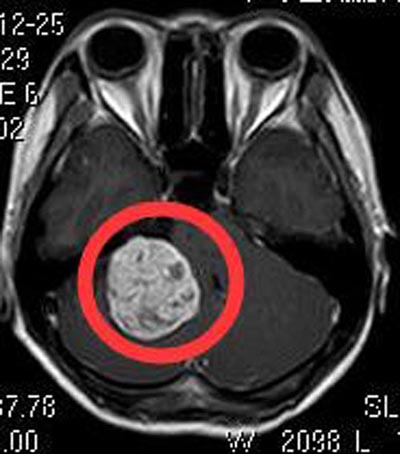

广东三九脑科医院进一步头颅MR检查显示:右侧桥小脑角区占位性病变,大小约4.0cm×3.9cm×2.8cm,脑干及右侧桥臂受压变形。四脑室受压变窄,考虑为听神经鞘瘤。夫妻俩积极地要求手术治疗。完善相关检查后,由综合神经外科鲁明主任主刀,在全麻下经内镜辅助行右侧桥小脑角区听神经瘤切除术,肿瘤呈黄白色,质中,三叉神经、舌咽神经受肿瘤压迫明显,予分块切除,右侧听神经、面神经、三叉神经、舌咽神经均保护完好。术后黄小姐没有出现并发症状。术后病理结果提示:神经鞘瘤。

▲手术前